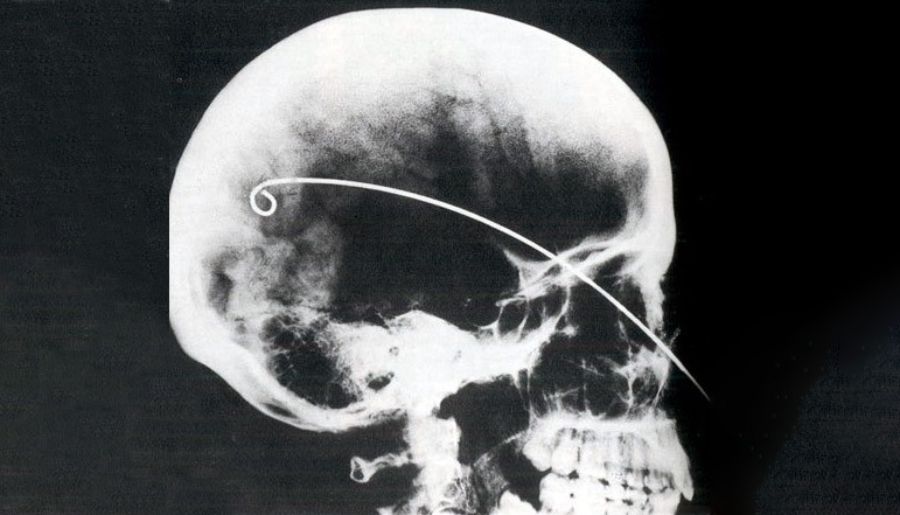

Önce çürüyebilecek iç vücut parçaları çıkarılır. Karnın sol kısmından açılan kesikle akciğer, mide, karaciğer ve bağırsak organları alınır. Kalp düşünmeyi sağladığından vücutta bırakılır. Pek bir işe yaradığı düşünülmeyen beyin ise kanca yardımıyla burundan çıkarılır. Rahipler sonra cesedi koruması ve kurutması için doğal natron tuzu ile kapladılar. Natron vücuttaki tüm nemi emer. Cesedi sarmak mumyalamanın son adımıdır. Bunun için reçineyle kaplanmış yüzlerce uzunlukta keten bez kullandılar.

- Beyin, demirden eğri bir parça ile burun deliğinden dışarı çekilir.